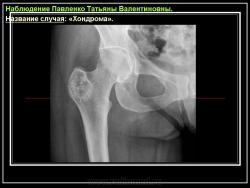

Энхондрома (син.: хондрома, центральная хондрома) — доброкачественная хрящевая опухоль, расположенная в костномозговом канале (интрамедуллярно). Встречается в 10 % случаев от общего числа доброкачественных опухолей костей. Считается, что она возникает из эктопически расположенных островков хряща, отщепившегося от пластинки роста на ранних этапах онтогенеза. В ряде случаев опухоль остается бессимптомной и обнаруживается случайно при рентгенологическом исследовании. В других случаях возникают боль и припухлость. Обычно болезненными становятся все энхондромы фаланг. Наиболее частая локализация: фаланги, главным образом, пальцев кистей, проксимальный конец плечевой кости, проксимальный или дистальный концы бедренной кости. При рентгенологическом исследовании в энхондроме определяются просветления с участками минерализации. Тень кости становится более широкой, кортикальный слой сохраняет целостность, но истончается. В редких случаях энхондрома имеет вид эксцентрически растущего экзофитного новообразования. Макроскопически опухоль представляет собой голубовато-белую полупрозрачную хрящевую ткань, в которую вкраплены желтоватые участки обызвествления. Опухоль состоит из отдельных хрящевых узелков, диаметр которых варьирует в пределах 1 см.

Хондрома (солитарная энхондрома, центральная хондрома) - доброкачественная опухоль из гиалинового хряща, расположенная в костномозговом канале кости. Обследовали 23 мужчины и 18 женщин с хондромой кости.

Рентгенологическая картина хондромы представляет четко очерченный опухолевый узел. Очаги минерализации в хондромах выглядят достаточно характерно и представлены очаговыми, глыбчатыми или кольцевидными , арочными отложениями извести. Полного разрушения кортикального слоя трубчатой кости с выходом опухолевых масс в мягкие ткани не наблюдается.